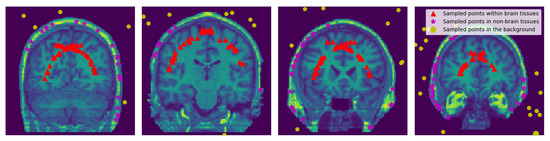

2.2.3. Sampling Points within the Brain, Non-Brain Tissues and Background